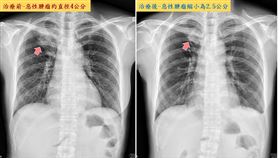

她肺腺癌第四期 靠這治療重回健身房

一名年約50歲的女性病患熱愛有氧運動,日前發現自己久...